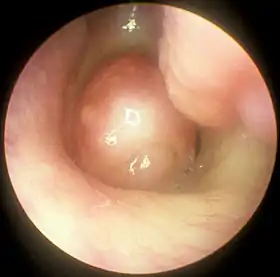

![]() Large nasal polyp (round mass, center), which is commonly treated and removed by FESS | |